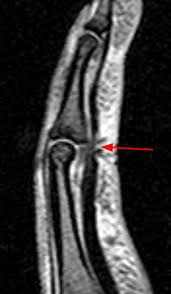

Quadrigia effect or dip joint flexion contracture occurs when profundus advancement of 1 cm or more. Flexor digitorum superficialis tendon transfer for intrinsic replacement. Fds / fdp flexor tendon repair dr. After the tenosynovectomy, the smooth gliding of tendons (fds and fdp) is confirmed by flexion and extension of the fingers (fig. Are we using this code correctly? At the level of the pip joint, the two slips of each fds tendon reunite deep to the fdp tendon to form the camper chiasm ( fig. Rupture of the flexor digitorum profundus (fdp) tendon from its distal attachment is commonly known as jersey finger. The flexor digitorum superficialis (fds) and flexor digitorum profundus (fdp) are the flexor tendons of the fingers, and the flexor pollicis longus (fpl) is the only thumb flexor.

This zone injuries called rugger jersey finger, which is a closed fdp avulsion occurring distal to the fds insertion. Please do not remove this. The flexor tendons travel distally from the forearm through the carpal tunnel and are named based on the forearm muscles from which they arise. However, flexor digitorum profundus to the long, ring, and small fingers always have a common muscle belly. The long and ring finger tendons lie superficial to the index and small finger tendons. They travel down the forearm and within the carpal tunnel. Primary or secondary without free graft, each tendon (26350) flexor tendon repair or advancement, single, not in no mans land; At the level of the pip joint, the two slips of each fds tendon reunite deep to the fdp tendon to form the camper chiasm ( fig. Flexor digitorum superficialis (fds) tendons fds tendons help bend the index, middle, ring, and small fingers at the middle finger joint. Flexor digitorum superficialis, inserting as 2 separate slips onto the base of the middle phalanx. Flexor digitorum superficialis tendon transfer for intrinsic replacement. Excision of tendon, finger, flexor separate procedure (26180) flexor tendon repair or advancement, single, not in no mans land; They are powered by a common muscle belly shared by all the fingers, which divides into 4 tendons.